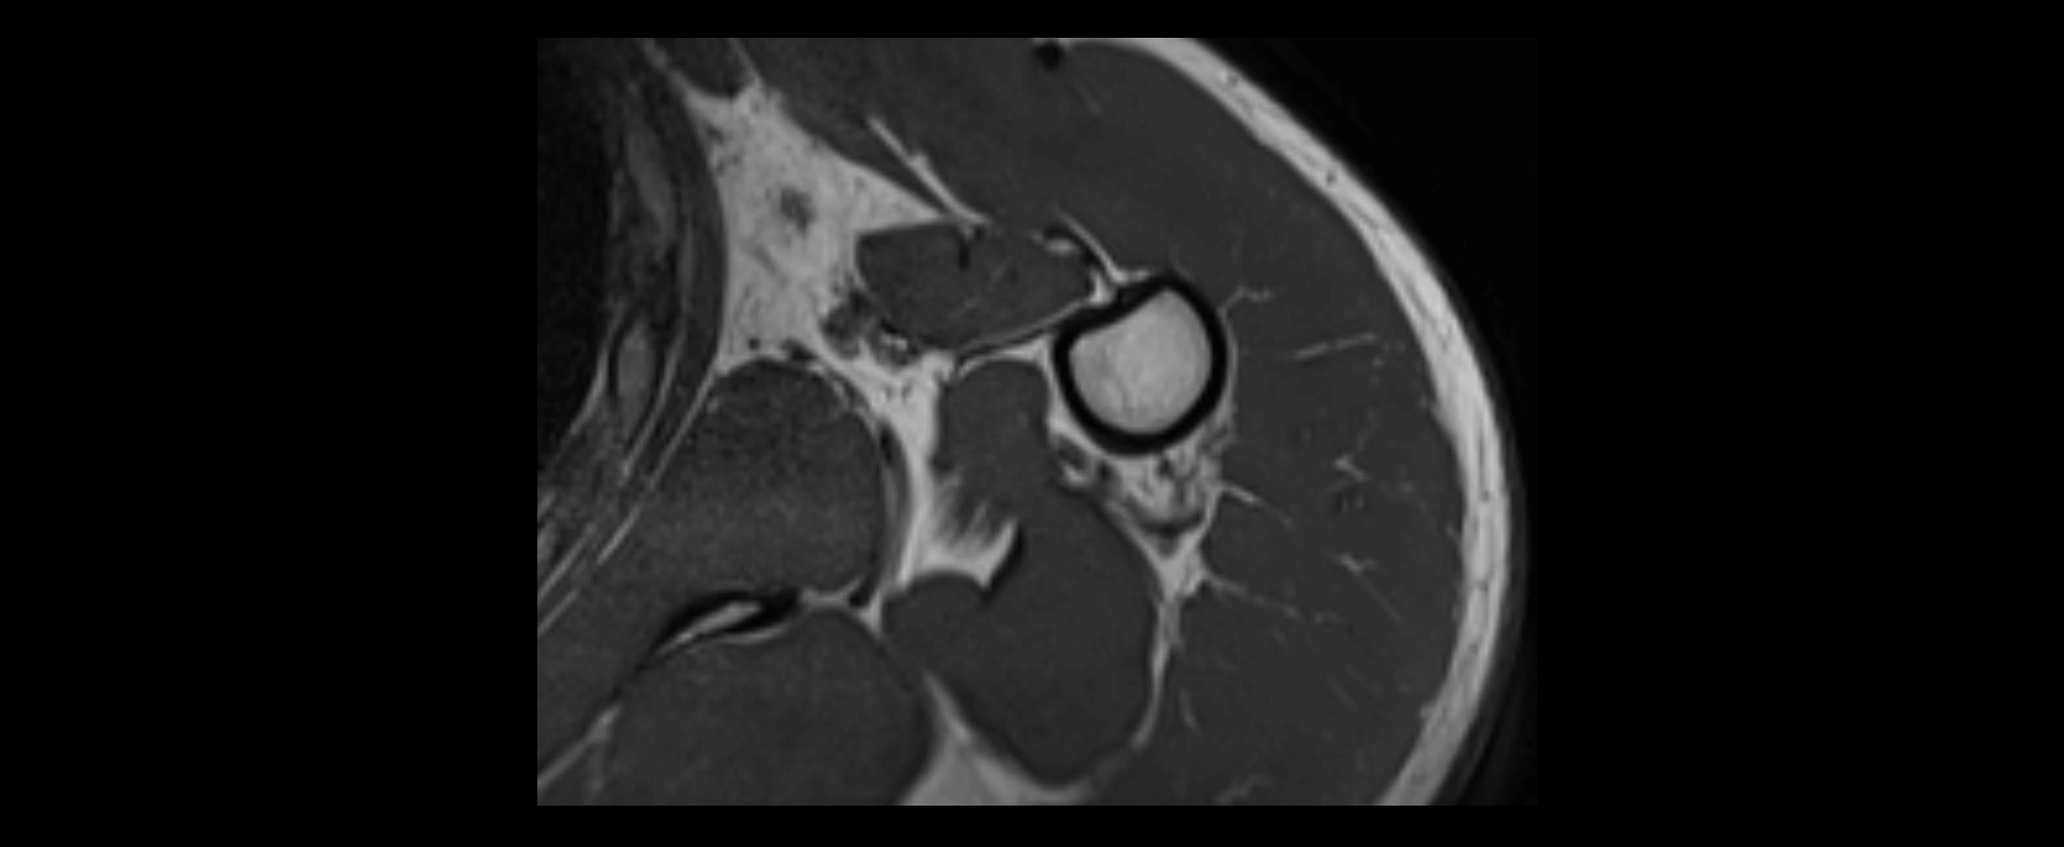

MRI images

image